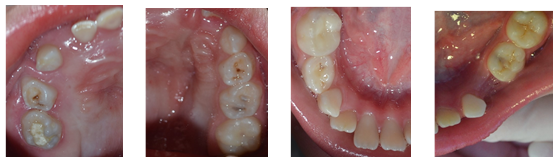

Al examen clínico de la cavidad bucal (Figs. 2,3,4,5 y 6), no se observaron lesiones en las mucosas, se identificaron atresia de la arcada dentaria superior con mordida cruzada unilateral en el lado derecho y mordida abierta anterior. Además, presencia generalizada de biopelicula microbiana sobre las superfícies dentales y sangrado gingival, un remanente radicular del diente 74, una restauración provisoria en mal estado en las caras oclusal y lingual del diente 85, así como lesiones microcavitadas activas de Caries dental en la cara oclusal de los dientes 26, 65 y 75.

Figs. 2,3,4,5 y 6: Aspectos clínicos iniciales total y por hemi arcada de la cavidad bucal de la niña al iniciar el tratamiento